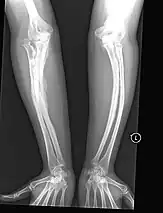

The main symptom of osteogenesis imperfecta is fragile, low mineral density bones; all types of OI have some bone involvement.[5] In moderate and especially severe OI, the long bones may be bowed, sometimes extremely so.[28] The weakness of the bones causes them to fracture easily—a study at the Endocrine Unit at the National Institute of Child Health in Karachi, Pakistan found an average of 5.8 fractures per year in untreated children.[29] Fractures typically occur much less after puberty, but begin to increase again in women after menopause and in men between the ages of 60 and 80.[1]: 486

OI type III causes osteopenic bones that fracture very easily, sometimes even in utero, often leading to hundreds of fractures during a lifetime;[24] early scoliosis that progresses until puberty; dwarfism (a final adult height frequently less than 4 feet or 120 centimetres); loose joints; and possible respiratory problems due to low rib cage volume causing low lung volumes.[5]: 1512

- Type V – Having the same clinical features as type IV, it can be clinically distinguished by observing a "mesh-like" appearance to a bone biopsy under a microscope. Type V can be further distinguished from other types of OI by the "V triad": an opaque band (visible on X-ray) adjacent to the growth plates; hypertrophic calluses (abnormally large masses of bony repair tissue) which form at fracture sites during the healing process; and calcification of the interosseous membrane of the forearm,[50] which may make it difficult to turn the wrist.[1]: 429 Other features of this condition may include pulled elbow, and, as in other types of OI, long bone bowing and hearing loss.[64] Cases of this type are caused by mutations in the IFITM5 gene on chromosome 11p15.5.[64][49] The separation of type V from type IV OI, its clinical type, was initially suggested even before its genetic cause was known, by Glorieux et al. in 2000.[50][65] Type V is relatively common compared to other genetically defined types of OI—4% of OI patients at the genetics department of the Brazilian Hospital de Clínicas de Porto Alegre were found to have it.[66]